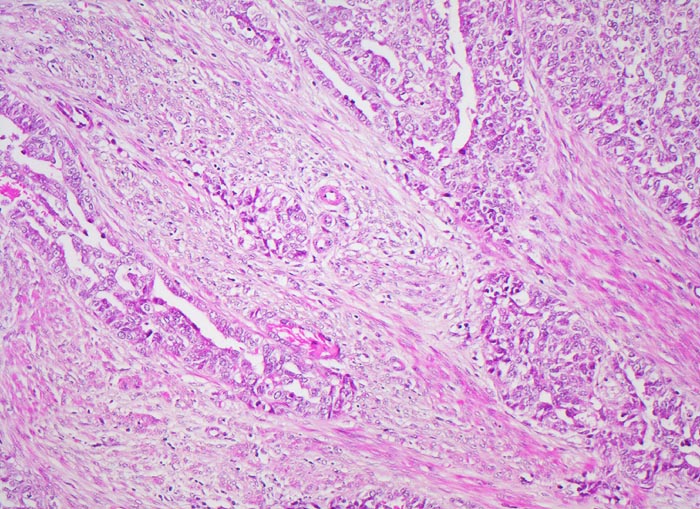

Morphologische Merkmale:

• Endomyometranes Gewebsfragment.

• Die rechte Seite des Uteruskavums wird ausgekleidet von flachem atrophem Endometrium. Im Cavum liegt ein Blutkoagel mit nekrotischem Detritus nach vorausgegangener diagnostischer Utersukurettage.

• Anstelle des Endometriums findet sich in der linken Hälfte des Uteruskavums ein Adenokarzinom bestehend aus architektonisch komplexen Drüsen. Die Drüsen liegen teils dos à dos ohne erkennbares Stroma zwischen zwei Drüsenschläuchen.

• Tumorzellverbände infiltrieren die glatte Muskulatur des Myometriums.

• Tumordrüsen ausgekleidet von mehrreihig angeordneten Tumorzellen mit hyperchromatischen polymorphen längsovalen Tumorzellkernen mit zahlreichen Mitosen. Die Morphologie der Tumordrüsen erinnert an proliferatives Endometrium.

• Anmerkung: Typischerweise ist das endometrioide Karzinom des Uterus als Folge des ursächlichen Hyperöstrogenismus assoziiert mit einem hyperplastischen Endometrium (siehe Präparat 148). Im Kurspräparat erscheint hingegen das nicht-neoplastische Endometrium nach vorausgegangener Kurettage atroph. Atrophes Endometrium findet sich sonst charakteristischerweise neben serösen Endometriumkarzinomen postmenopausaler Patientinnen. Das sollte der Kliniker dem Pathologen mitteilen: